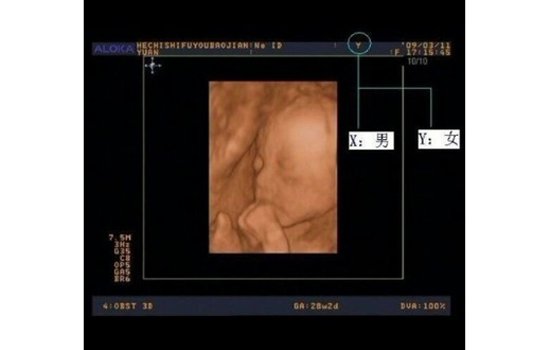

b超怎么看胎儿性别之看YX字母

妈妈在中晚期做B超时,可留心任意一张B超单(早孕的不能显示的),看看B超图像上最顶是不是有一橫行,橫行中间会有显示Y或X的字母,如果是Y就代表你怀的是女孩,X就是男孩。有的地方很严格,B超单上可能没有,那么也可以采取下面的方法来判断。